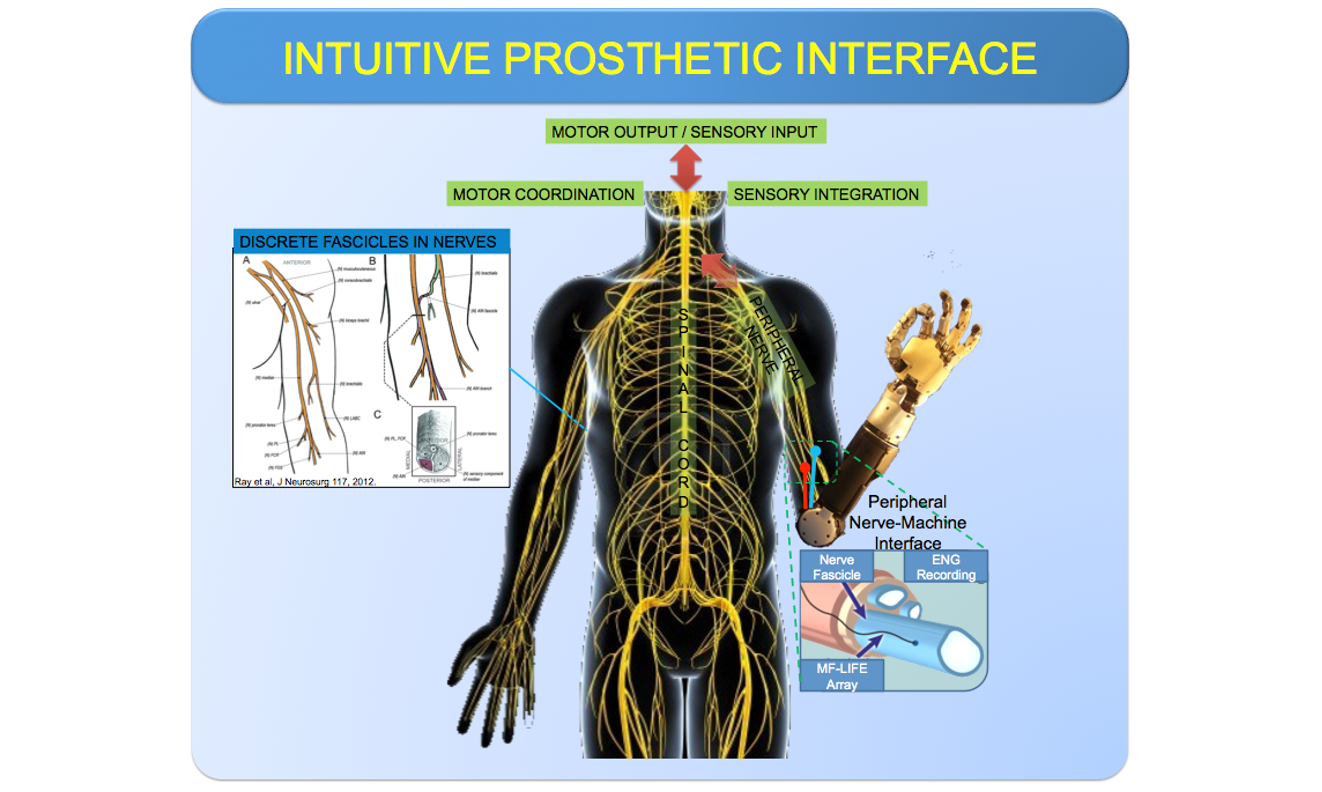

Building intuitive prosthetic interface for seamless motor coordination in amputee patients